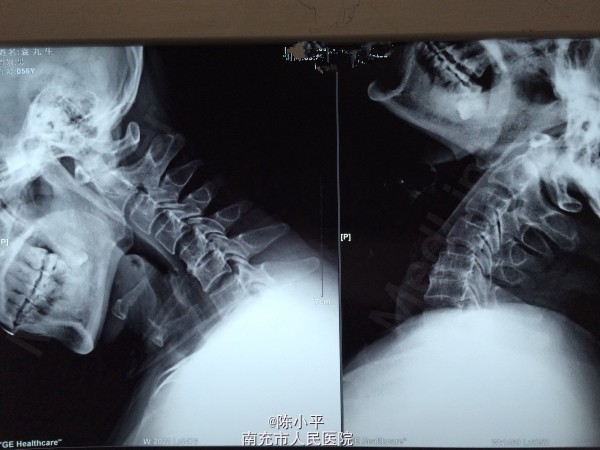

患者男性,56岁,自述肩部无力半年多,会诊后诊断为肌萎缩型颈椎病(颈4.5椎体不稳、颈5/6椎间盘突出),查体:左上肢肌力正常,左拇指麻木,右上肢肱三头肌、右手握力约4级,小指麻木,虎口区肌肉萎缩,双下肢肌力、感觉正常。双手霍夫曼征阴性。